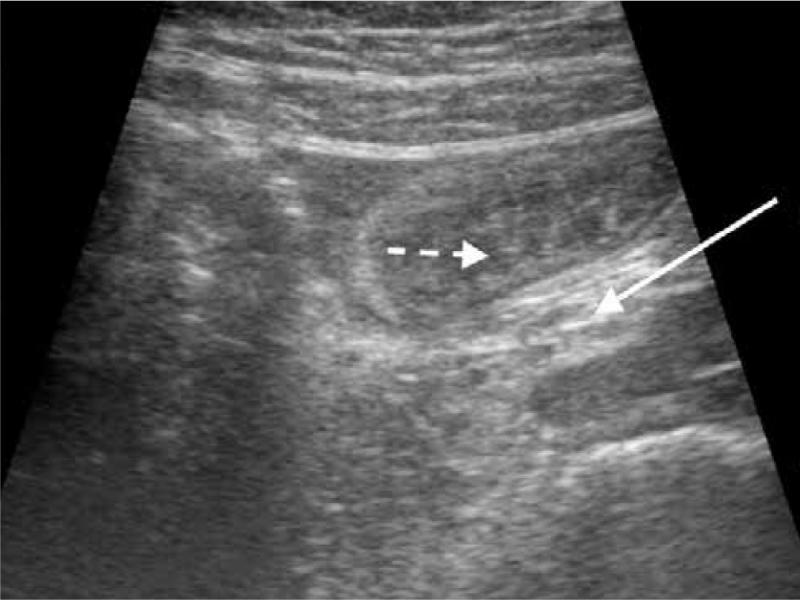

Fig. 1.

A. Ultrasound of the abdomen in the axial plane showing a lesion (solid arrow) in the umbilical region with multiple concentric hyperechoic and hypoechoic rings – target sign or doughnut sign appearance (

B, C

). On tracing the lesion further, eccentric hyperechoic mesentery (solid arrow) appears

A. Ultrasound of the abdomen in the axial plane showing a lesion (solid arrow) in the umbilical region with multiple concentric hyperechoic and hypoechoic rings – target sign or doughnut sign appearance ( B, C ). On tracing the lesion further, eccentric hyperechoic mesentery (solid arrow) appears